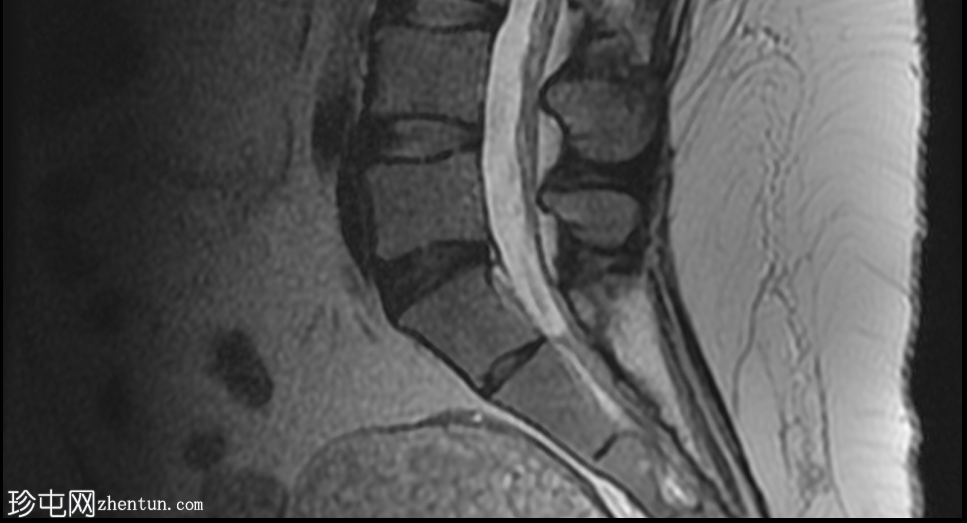

轴位

平扫

可见一主要为囊性肿块,大小为10.1 x 7.3 x 8厘米,囊内含有脂肪球。囊壁可见钙化,并对直肠乙状结肠造成压迫。